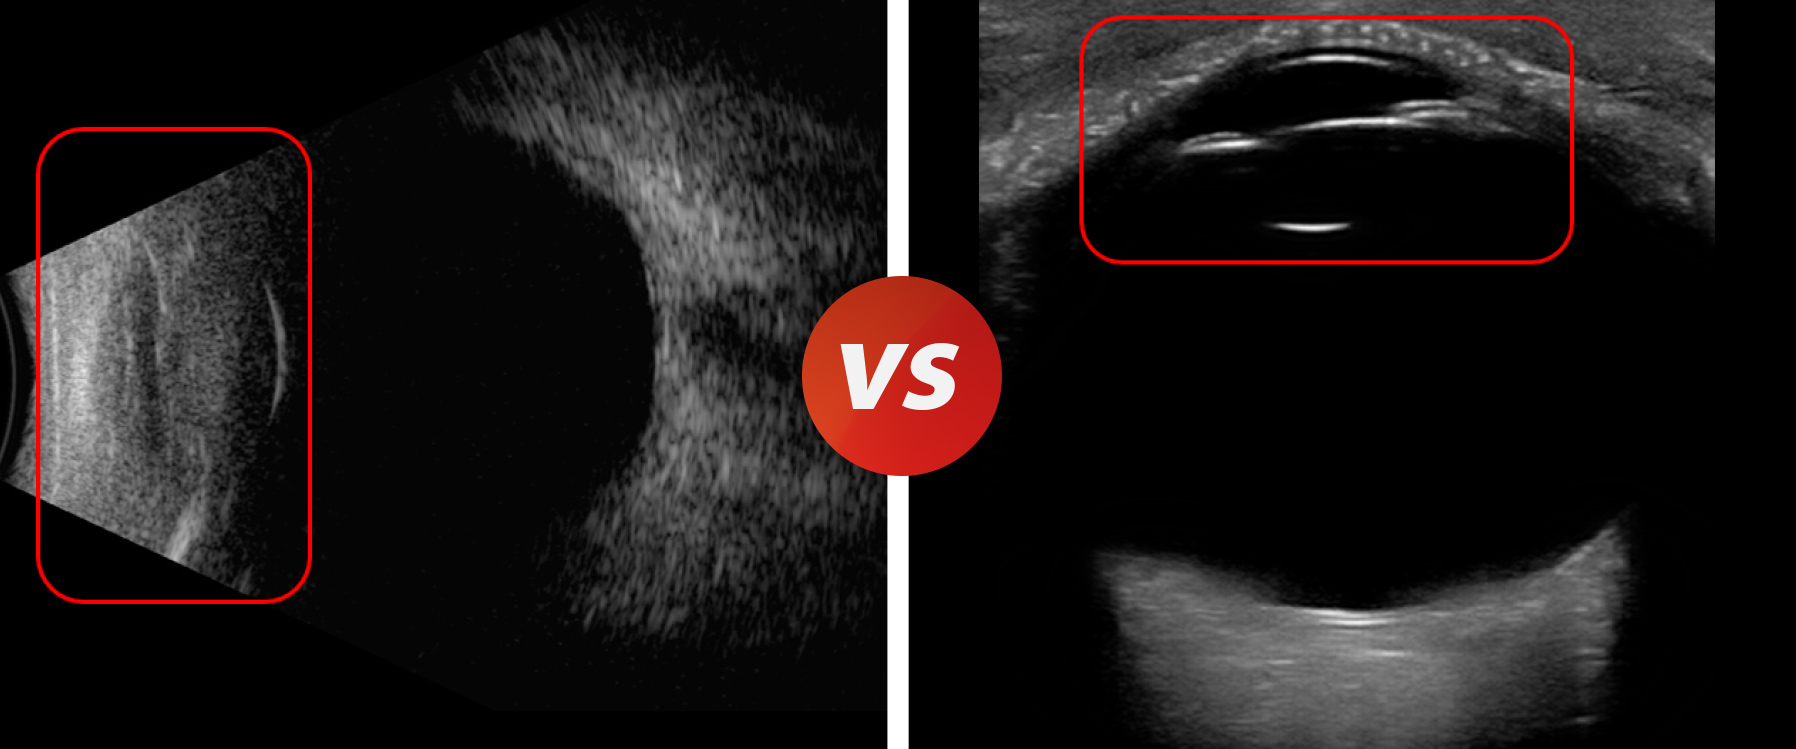

除了优化图像分辨力、穿透力,相比传统眼科超声(下图左),彩超 B 模式成像(下图右)还能解决近场盲区和图形畸变等局限。

正常眼的传统眼科 B 超成像

迈瑞眼科彩超 B 模式成像

眼科 B 超眼前节存在盲区(下图左),而彩超 B 模式下的眼前段结构成像(下图右)则没有这种痛点,甚至眼睑、睑板腺,泪腺等结构都清晰可见。

眼外伤

传统眼科 B 超成像,前房情况不清

迈瑞眼科彩超 B 模式成像,前房术后缝合情况清晰可见